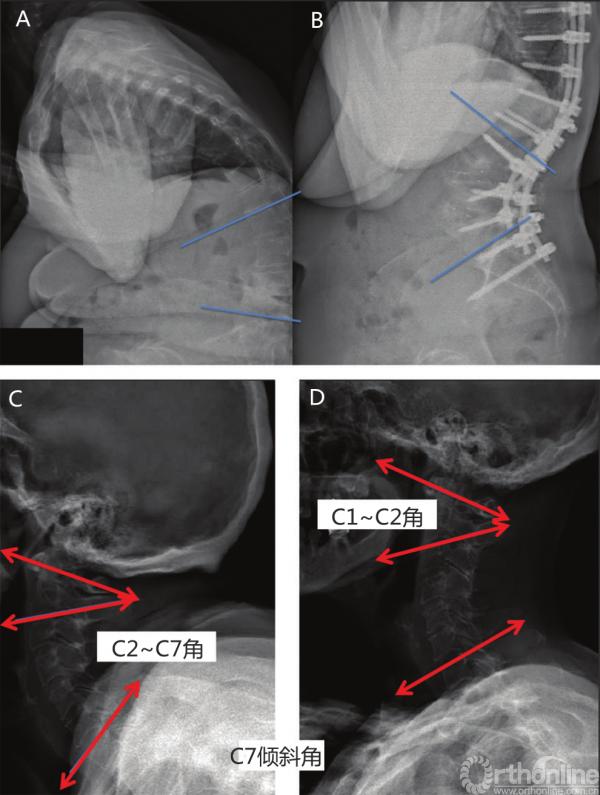

向上力线的其他表现包括矫正腰椎后凸的患者接受大型截骨术矫正后,颈椎前凸角度增加(图3-37,图3-38)。

图3-37

图3-37 腰椎截骨术后的“向上力线”

A.术前腰椎X线;B.术后腰椎X线;C.术前颈椎X线;D.术后颈椎X线。C2~C7角减小较多,C1~C2角减小较小